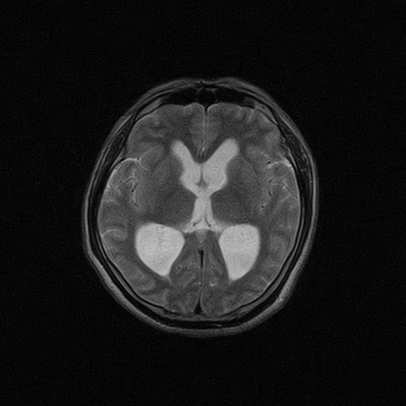

标题: MRI2064:少见病例。男性52,视力下降多年。 [打印本页]

标题: MRI2064:少见病例。男性52,视力下降多年。

四脑室区见混杂信号占位影,脑室系统扩张明显,临近结构显著受压称位,患者52岁,多考虑室管膜瘤可能性大

考虑第四脑室室管膜瘤并阻塞性脑积水。

考虑第四脑室室管膜瘤并梗阻性脑积水;部分性空蝶鞍;左侧上颌窦粘膜下囊肿。

考虑第四脑室室管膜瘤【血供丰富血管母细胞瘤可能】并梗阻性脑积水;部分性空蝶鞍;左侧上颌窦粘膜下囊肿。

比较典型的脉络丛乳头状瘤并脑积水,鉴别小脑蚓部血管母细胞瘤。